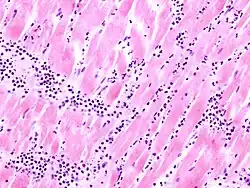

Mikro: Interstitielles lymphozytäres Infiltrat (kleine blaue Zellen), kaum Nekrosen.